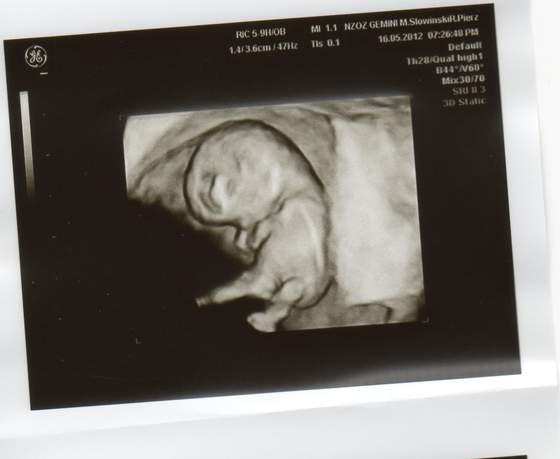

Po wczorajszej wizycie wstawiam obiecane zdjęcia mojego maleństwa :-) Morfologie mam idealną zato w moczu liczne bakterie Dostałam prenatal uro care i mam brać przez 10-12 dni i powtórzyć badanie moczu. Kolejna wizyta za 4 tyg :-)

Fiolka też mam podobne ale jak mi lekarz pokazał bijące serduszko to mu powiedziałam, że chcę ładne zdjęcie i mi na 3d przerzucił :-) zrobił zdjęcie z boczku, później powiedział "troszkę przodem, troszkę tyłem" i mam 3 śliczne fotki :-) A na koniec "no maluszku damy ci już spokój" - oj na fajnego lekarza trafiłam

A twój brząc wygląda pewnie identycznie tylko parę mm mniejszy :-)

Fiolka nie zeskanowałam z czystego lenistwa A drukarkę mam w innym pokoju i muszę lapa targać z kablami bo bateria kaput Jak coś to jutro zeskanuję ale moje nie jest takie ładne jak twoje bo nie widać tak rączek i nóżek - raczej taką rybkę